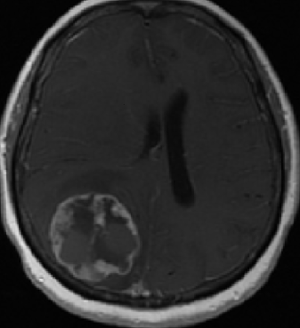

МР-диагностика опухолевого поражения головного мозга или метастазов в головной мозг